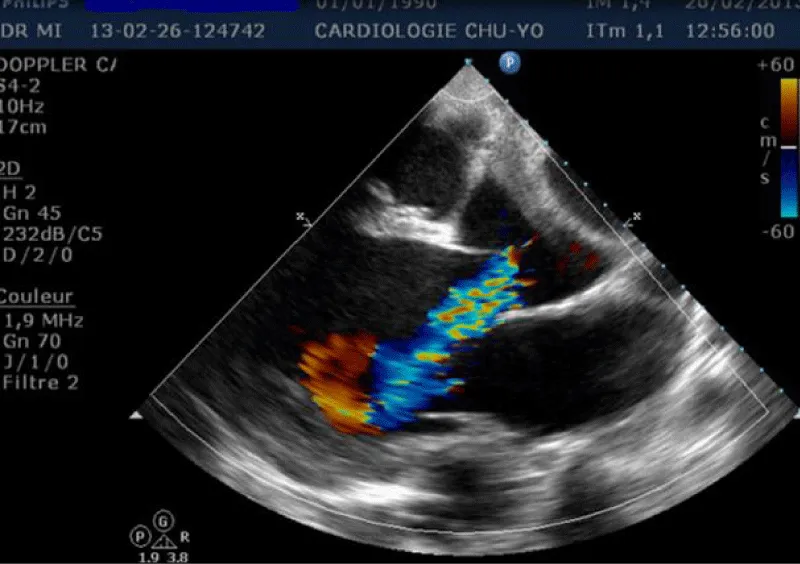

Transthoracic echocardiography (Figures 3,4) found a dilated aortic root (52 mm) with an ultrasound image of the intimal flap, and significant bi-ventricular dilation (left ventricular end-diastolic diameter of 72 mm). Systolic functions of both ventricles were severely impaired (LVEF of 24% and TAPSE of 10 mm). There was severe aortic regurgitation with a regurgitant orifice area of 35 mm². Dissection of an aortic aneurysm on dilated cardiomyopathy was diagnosed and confirmed by aortic CT scan (Figure 5); it was a type A aortic dissection with very severe dilation of the aortic root at the origin of the first branch of the supra-aortic trunks. A Type B dissection coexisted along, with an aortic dilation beginning far from the origin of the last branch of the supra-aortic trunks up to the iliac bifurcation. The Marfan disease was diagnosed despite the absence of genetic testing and a family history of the syndrome. An ophthalmological assessment could not be carried out. Medical treatment with diuretics, vasopressin amines, and analgesics was started and enabled slight improvement. The patient was later referred for surgical management through the financial support of a philanthropic sponsor. He was operated on March 7th, 2013 under cardiopulmonary bypass, using the Tirone David procedure. During surgery, the impression of two separate aortic dissections was confirmed: the former one of type B which previously went unnoticed, and the recent one of type A which determined the patient current clinical condition. After surgery, congestive heart failure was persistent, but during follow-up in the outpatient unit, the clinical condition remained stable under diuretic, ACE inhibitor, and oral anticoagulation. Unfortunately, the patient died four years later in 2017, due to poor medical follow-up.

Figure 4: Transthoracic heart ultrasound para-sternal long axis incidence: dilatation of the ascending aorta and aortic leakage directed toward the large mitral valve.